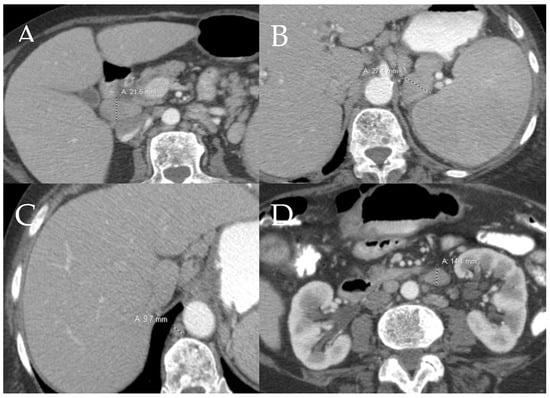

6.2.2. Liver and Spleen